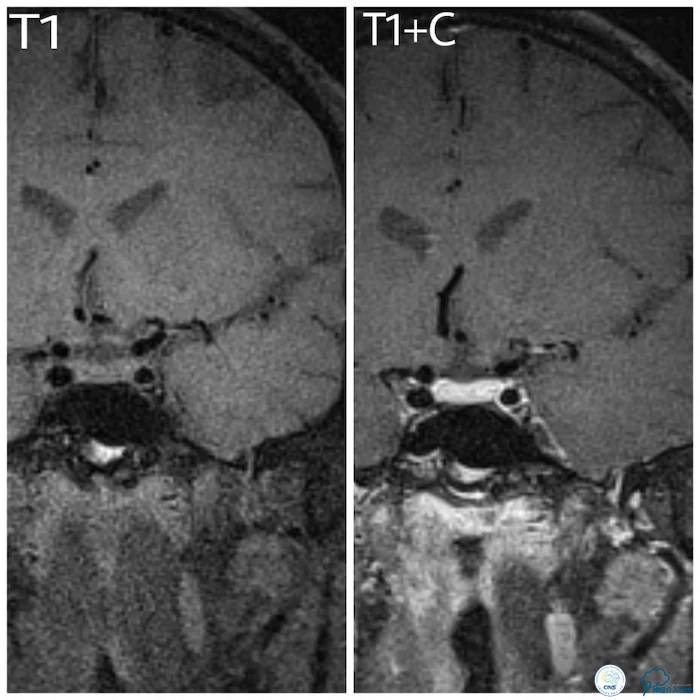

HRMRI:左大脑中动脉M1段前下管壁增厚,呈不均匀等T1等长PD信号影。增强扫描显示局部明显强化,管腔明显狭窄。考虑左侧大脑中动脉M1段前下壁斑块形成,管腔明显狭窄(图7)。

图7